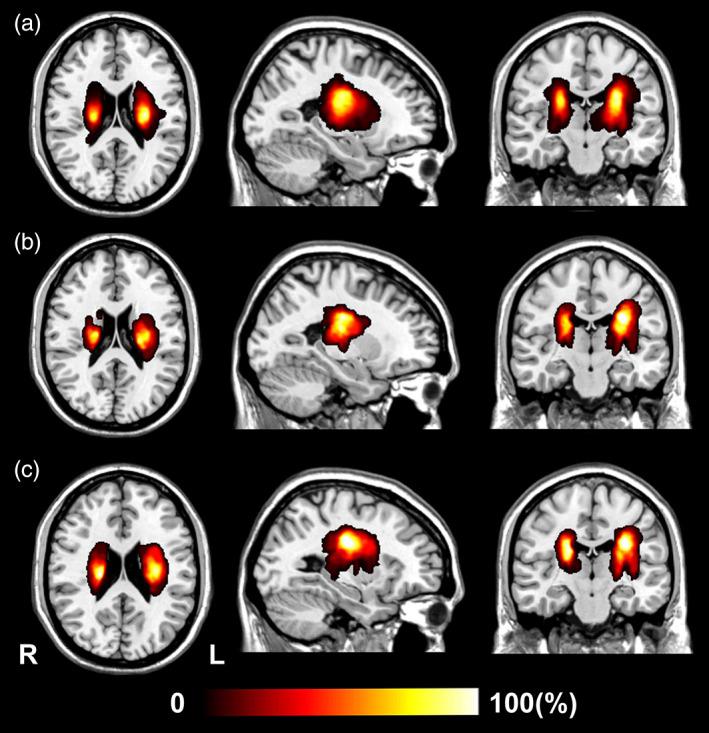

Subcortical ischemic stroke can lead to persistent structural changes in the cerebral cortex. The evolution of cortical structural changes after subcortical stroke is largely unknown, as are their relations with motor recovery, lesion location, and early impairment of specific subsets of fibers in the corticospinal tract (CST). In this observational study, cortical structural changes were compared between 181 chronic patients with subcortical stroke involving the motor pathway and 113 healthy controls. The impacts of acute lesion location and early impairments of specific CSTs on cortical structural changes were investigated in the patients by combining voxel-based correlation analysis with an association study that compared CST damage and cortical structural changes. Longitudinal patterns of cortical structural change were explored in a group of 81 patients with subcortical stroke using a linear mixed-effects model. In the cross-sectional analyses, patients with partial recovery showed more significant reductions in cortical thickness, surface area, or gray matter volume in the sensorimotor cortex, cingulate gyrus, and gyrus rectus than did patients with complete recovery; however, patients with complete recovery demonstrated more significant increases in the cortical structural measures in frontal, temporal, and occipital regions than did patients with partial recovery. Voxel-based correlation analysis in these patients showed that acute stroke lesions involving the CST fibers originating from the primary motor cortex were associated with cortical thickness reductions in the ipsilesional motor cortex in the chronic stage. Acute stroke lesions in the putamen were correlated with increased surface area in the temporal pole in the chronic stage. The early impairment of the CST fibers originating from the primary sensory area was associated with increased cortical thickness in the occipital cortex. In the longitudinal analyses, patients with partial recovery showed gradually reduced cortical thickness, surface area, and gray matter volume in brain regions with significant structural damage in the chronic stage. Patients with complete recovery demonstrated gradually increasing cortical thickness, surface area, and gray-matter volume in the frontal, temporal, and occipital regions. The directions of slow structural changes in the frontal, occipital, and cingulate cortices were completely different between patients with partial and complete recovery. Complex cortical structural changes and their dynamic evolution patterns were different, even contrasting, in patients with partial and complete recovery, and were associated with lesion location and with impairment of specific CST fiber subsets.

皮质下缺血性卒中可导致大脑皮层持续的结构性改变。皮质下卒中后皮质结构变化的演变在很大程度上是未知的,其与运动恢复、病变部位以及皮质脊髓束(CST)中特定纤维亚群的早期损伤的关系也未知。在这项观察性研究中,比较了 181 例涉及运动通路的皮质下卒中慢性患者和 113 例健康对照者之间的皮质结构变化。通过将体素相关分析与关联研究相结合,研究了患者急性病变部位和 CST 特定亚群的早期损伤对皮质结构变化的影响,在关联研究中比较了 CST 损伤和皮质结构变化。使用线性混合效应模型对一组 81 例皮质下卒中患者进行了皮质结构变化的纵向研究。在横断面分析中,部分恢复的患者较完全恢复的患者在感觉运动皮层、扣带回和直回的皮质厚度、表面积或灰质体积减少更显著;然而,完全恢复的患者在额、颞和枕叶的皮质结构测量值的增加更显著。这些患者的体素相关分析显示,起源于初级运动皮层的 CST 纤维的急性卒中病变与慢性阶段对侧运动皮层的皮质厚度减少有关。壳核的急性卒中病变与慢性阶段颞极的表面积增加有关。起源于初级感觉区的 CST 纤维的早期损伤与枕叶皮质的皮质厚度增加有关。在纵向分析中,部分恢复的患者在慢性阶段有显著结构损伤的脑区表现出逐渐减少的皮质厚度、表面积和灰质体积。完全恢复的患者在额、颞和枕叶区域表现出逐渐增加的皮质厚度、表面积和灰质体积。部分和完全恢复患者的额、枕和扣带回皮质的慢结构变化方向完全不同。部分和完全恢复患者的皮质结构变化复杂,且其动态演变模式不同,甚至相互矛盾,这与病变部位和特定 CST 纤维亚群的损伤有关。